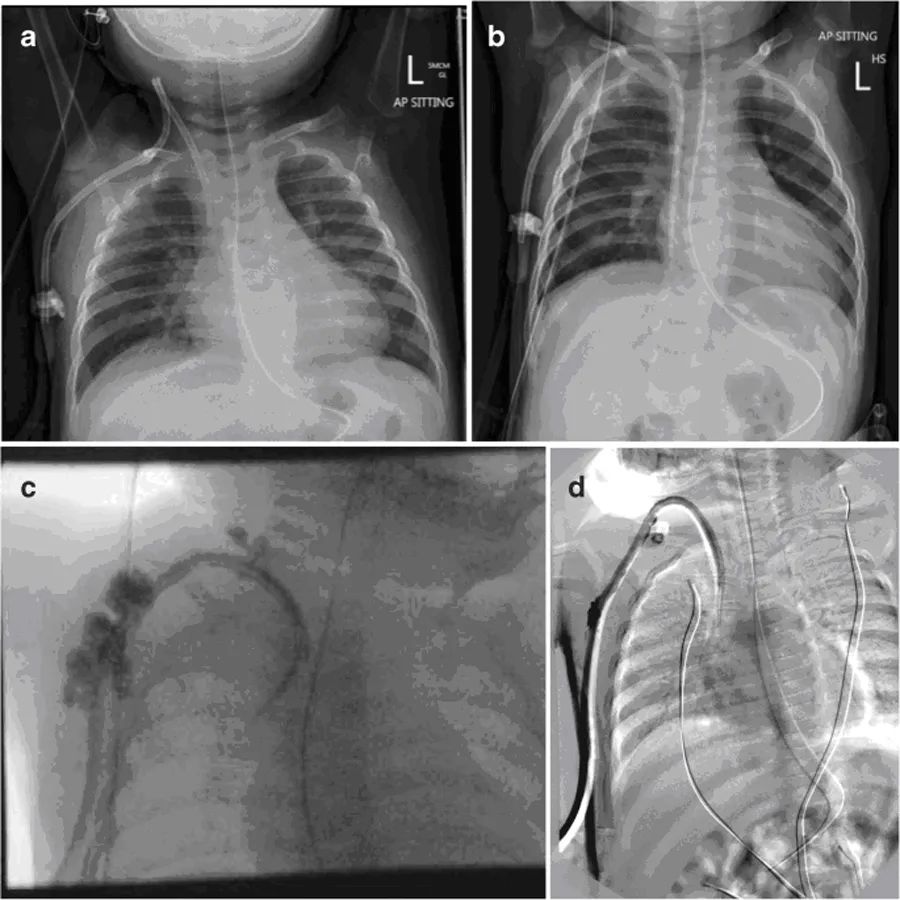

第二天,两个透析导管腔都很难抽吸,冲洗时需要高压。X光片显示导管尖端在上腔静脉中上部,提示导管位置异常(图1a)。导管流量小,无法血液透析,患者第二天返回手术室进行调整。在确认颈部入口处有扭结后,导管被重新定位。两个腔在术中冲洗和抽吸良好。患者在手术后立即开始第一次血液透析,持续2小时,患儿耐受良好,治疗成功。

在随后的血液透析过程中,发现动脉腔抽吸困难,血流速度减慢。静脉腔功能良好。置入后11天,x光片显示导管尖端在右心房内向下移动(图1b)。由于静脉回流压力高(>200mmHg)和次优最大血流量(30ml/min),血液透析提前终止。给予tPA,但没有令人满意的改善。最大血流速度可达到50ml/分钟,但回流压力仍然过高(250mmHg)。

将导管更换为Medcomp®10 Fr×15 cm分离式导管®,通过一个稍微位于前一切口内侧的新切口插入右侧颈内静脉。选择大口径、短导管,以达到更高的流速和避免导管尖端的移动。影像增强确认位置,两腔在手术室冲洗和抽吸良好。放置导管后,立即尝试血液透析,但尽管冲洗良好,动脉腔仍无法抽吸,患儿明显疼痛。影像学检查显示对比剂似乎从多个部位逃逸到周围组织中(图1c)。立即取出导管,用一个位于右心房的12-Fr剥离式鞘管通过上一个切口替换成新导管。在检查或冲洗拆除的管线时,未发现断裂迹象。影像增强确认了新透析通路的位置,在肝素封管前,两个管腔在手术室抽吸和冲洗良好。

在次日开始血液透析时,动脉压过高(>250 mmHg),血流速度不能超过30 mL/min。更换通路,之后达到50 mL/min的血流速度。然而,几分钟后,患儿表现出疼痛,并在出口处发现出血。影像学检查确认导管位置正常,但是,显示造影剂渗入周围组织(图1d)。